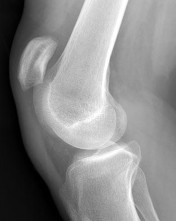

Question 1:

A 45-year-old recreational athlete presents with acute medial knee pain after feeling a 'pop' while deep squatting. MRI demonstrates an extrusion of the medial meniscus of 4 mm and a complete radial tear at the posterior root. Which of the following best describes the primary biomechanical consequence of this specific injury pattern?

Correct Answer: Loss of hoop stresses leading to peak contact pressures equivalent to a total meniscectomy

A posterior medial meniscus root tear disrupts the circumferential hoop stresses that the intact meniscus relies on to dissipate axial loads. Biomechanical studies demonstrate that a posterior root tear is functionally equivalent to a total meniscectomy in terms of decreasing contact area and dramatically increasing peak tibiofemoral contact pressures, leading to rapid chondrolysis and osteoarthritis if left untreated.